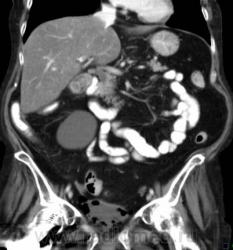

О чём могут говорить такие "газовые структуры" в области мочевого пузыря?

Наличие газа в мочевом пузыре может говорить о многом. Например стоял катетр Фолея, состояние после цистоскопии, эмфизематозный цистит, наличие фистулы.

А, чем именно, будет характеризоваться эмфизематозный цистит? При нем "пузырьки газа" локализуются в слизистой оболочке или где?

В просвете, может быть и в самой стенке. Смотрите здесь:

процесс в стенке в данном случае.

У женщины киста правой почки, подозрение на жировой гепатоз, стержень в головке и шейке правого бедра (остеосинтез). А про воздух возле/в стенке мочевого пузыря... не было ли оперативного вмешательства в малом тазу? И без аксиальных срезов явно я бы не сказала, где конкретно воздухblush...

Фик с ней с кистой... И какая разница аксиалы и короналы... Да, толстоваты срезы, эффект усреднения. Но я бы думал в сторону язвенного/гангренозного цистита (эмфизематозного цистита). Естественно, анамнез и клиника и всё встанет на свои места. На состояние после катерера не очень похоже...